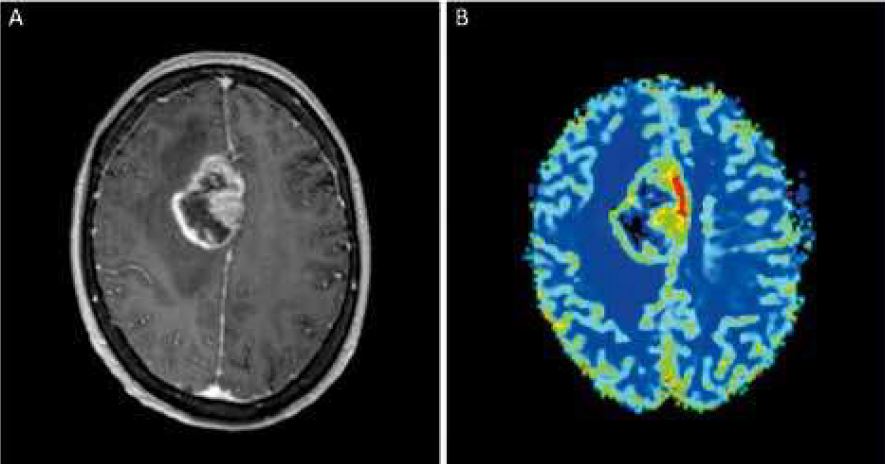

• Problèmes neurodégénératifs (Alzheimer, Parkinson...)